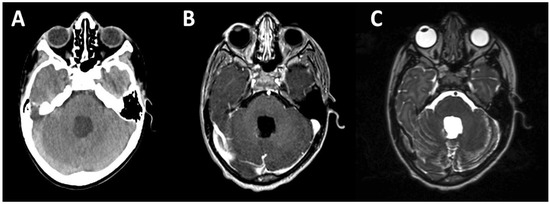

- Gunther, J.R.; Sato, M.; Chintagumpala, M.; Ketonen, L.; Jones, J.Y.; Allen, P.K.; Paulino, A.C.; Okcu, M.F.; Su, J.M.; Weinberg, J.; et al. Imaging Changes in Pediatric Intracranial Ependymoma Patients Treated With Proton Beam Radiation Therapy Compared to Intensity Modulated Radiation Therapy. Int. J. Radiat. Oncol. Biol. Phys. 2015, 93, 54–63. [Google Scholar] [CrossRef] [PubMed]